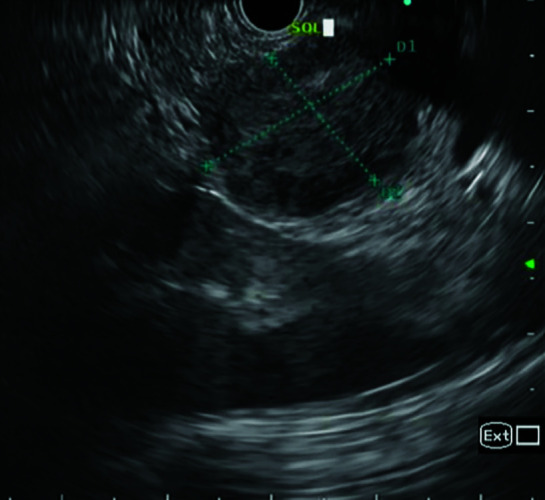

{"title":"Solid Pseudopapillary Neoplasm of the Pancreas: Unraveling Insights from a Single Institutional Study Emphasizing Preoperative Diagnosis of a Rare Tumor.","authors":"Loganathan Jayapal, Santhosh R Kumar, Gilbert Samuel Jebakumar, Siddesh S Tasgaonkar, Sudeepta Kumar Swain, Venkatesh Munikrishnan, Tirupporur Govindaswamy Balachandar","doi":"10.5005/jp-journals-10018-1394","DOIUrl":null,"url":null,"abstract":"<p><strong>Aim: </strong>Solid pseudopapillary neoplasm (SPN), a slow-growing pancreatic tumor with a vague clinical presentation and non-specific radiological features, is rather uncommon. We share our experience emphasizing on preoperative diagnosis and the correlation with final histopathological examination.</p><p><strong>Materials and methods: </strong>This is a retrospective analysis of the 468 patients who underwent pancreas-related surgery at our institution between January 2013 and July 2022. Demographic characteristics, symptoms at presentation, preoperative serum calcium carbohydrate antigen (CA 19-9), lesion characteristics on cross-sectional diagnostic imaging, surgical technique, complications in postoperative period, length of stay, histopathological features, and 3-year follow-up findings of the patients with SPN of pancreas were evaluated.</p><p><strong>Results: </strong>The male-to-female ratio was 1:11 and the mean age at presentation was 33.3 ± 9.5 years. Upper abdomen discomfort was the most common presenting complaint (91%). And five patients had findings suggestive of SPN on preoperative CECT abdomen, and the remaining six individuals were diagnosed solely based on final histological examination. The tumor's median diameter was 5.6 cm (range, 4.1-7.9). The distal body and tail of pancreas was the most common location (63%), followed by the head (36%), and was managed with distal pancreatectomy with or without spleen preservation and Whipple's procedure, respectively. One patient developed grade III Clavien-Dindo complication. The average length of in-hospital stay was 8.27±2.72 days. None of the patients had recurrence on follow-up.</p><p><strong>Conclusion: </strong>Solid pseudopapillary neoplasm of the pancreas is often misdiagnosed preoperatively. Endoscopic ultrasound-guided FNA with IHC will be beneficial to diagnose it preoperatively especially in small-sized tumors with atypical features. Complete surgical resection with adequate margins without routine lymphadenectomy is curative in resectable tumors.</p><p><strong>How to cite this article: </strong>Jayapal L, Kumar SR, Jebakumar GS, <i>et al</i>. Solid Pseudopapillary Neoplasm of the Pancreas: Unraveling Insights from a Single Institutional Study Emphasizing Preoperative Diagnosis of a Rare Tumor. Euroasian J Hepato-Gastroenterol 2023;13(2):50-54.</p>","PeriodicalId":516317,"journal":{"name":"Euroasian journal of hepato-gastroenterology","volume":"13 2","pages":"50-54"},"PeriodicalIF":0.0000,"publicationDate":"2023-07-01","publicationTypes":"Journal Article","fieldsOfStudy":null,"isOpenAccess":false,"openAccessPdf":"https://www.ncbi.nlm.nih.gov/pmc/articles/PMC10785128/pdf/","citationCount":"0","resultStr":null,"platform":"Semanticscholar","paperid":null,"PeriodicalName":"Euroasian journal of hepato-gastroenterology","FirstCategoryId":"1085","ListUrlMain":"https://doi.org/10.5005/jp-journals-10018-1394","RegionNum":0,"RegionCategory":null,"ArticlePicture":[],"TitleCN":null,"AbstractTextCN":null,"PMCID":null,"EPubDate":"","PubModel":"","JCR":"","JCRName":"","Score":null,"Total":0}

Conclusion: Solid pseudopapillary neoplasm of the pancreas is often misdiagnosed preoperatively. Endoscopic ultrasound-guided FNA with IHC will be beneficial to diagnose it preoperatively especially in small-sized tumors with atypical features. Complete surgical resection with adequate margins without routine lymphadenectomy is curative in resectable tumors.